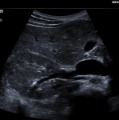

ACUSON P500 Ultrasound System

●可攜式超音波儀器隨時隨地提供高品質影像成像